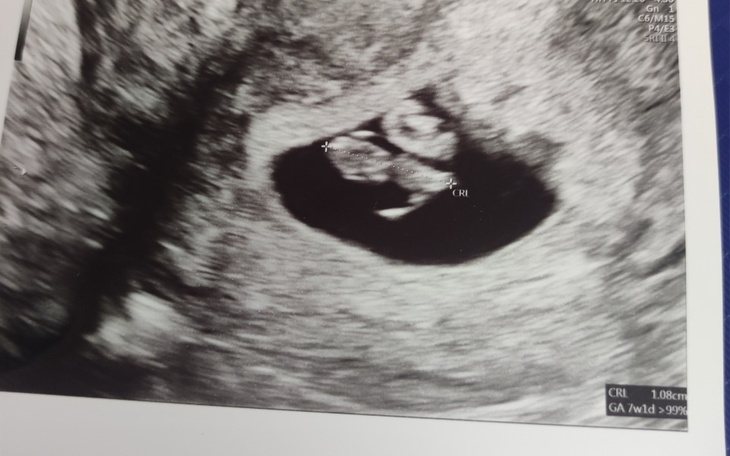

Hello. I am forced to set up a fundraiser for fetal genetic testing. I am 8 weeks pregnant. Unfortunately, we have a genetic load on my father's side (father's sister gave birth to a child with a genetic defect where the child died). My eldest son Tiberius was born with a heart defect (perimembranous interventricular defect). The attending physician suggested that I do genetic tests, unfortunately I am not able to pay the whole amount, so I decided to collect at least some of it. If you can help, donate even a buck or share.